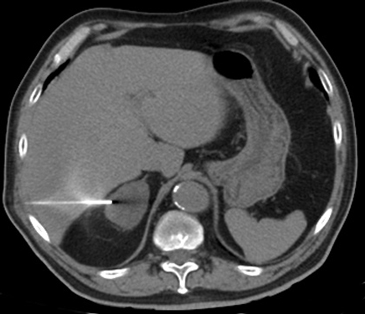

En la TC no contrastada las glándulas suprarrenales normales son homogéneas y simétricas, con una densidad muy similar a la del parénquima renal adyacente (Figura 1 a). Con un medio de contraste ev la glándula suprarrenal se opacifica en forma homogénea, similar al hígado o al bazo (Figura 1 b). Si la cantidad de tejido adiposo retroperitoneal es abundante las glándulas suprarrenales pueden aparecer enteramente rodeadas por grasa y su delimitación es más fácil (Figura 2 a); lo inverso ocurre en pacientes muy delgados con escasa grasa retroperitoneal (Figura 2 b). En RM, en secuencias ponderadas en T1 y T2 convencionales tienen una intensidad de señal homogénea, hipointensa respecto de la grasa adyacente e iso o hipointensa con respecto del parénquima hepático (Figura 3 a y b). En los cortes coronales se aprecia mejor la forma y la posición de las glándulas suprarrenales (Figura 3 c).

Figura 3. Glándula suprarrenal normal en resonancia magnética. (a) Cortes axial ponderado en T1 la señal de la glándula normal (flecha negra) es hipointensa respecto a la grasa retroperitoneal e isointensa respecto al parénquima hepático. (b) Cortes axial ponderado en T2 en que se muestra la glándula suprarrenal derecha (flecha blanca) y (c) corte coronal ponderado en T2 en que se muestra la glándula suprarrenal derecha (flecha blanca) y la glándula suprarrenal izquierda (flecha negra) con similares características de intendidad de señal. 3. Causas y prevalencia de las lesiones suprarrenales